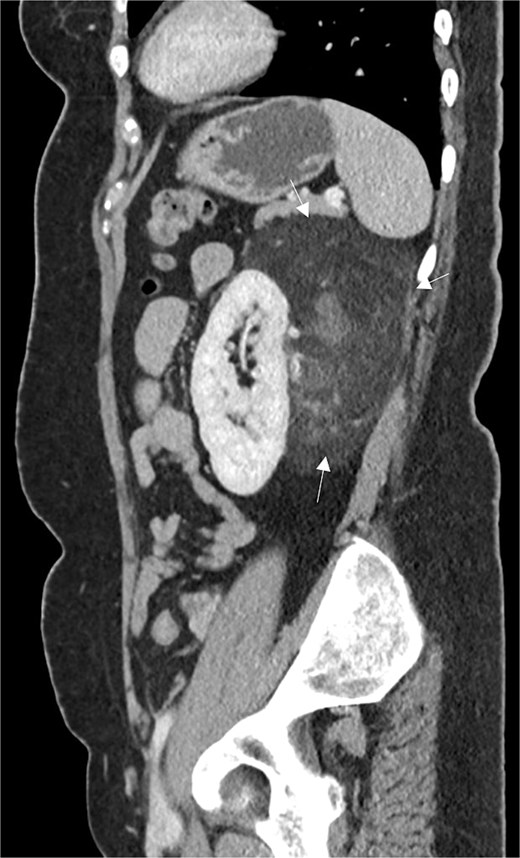

A 54-year-old non-smoker, post-menopausal female, presented to the outpatient clinic with vague abdominal pain (score of 4/10) radiating to the back. Her past medical history included hypertension, diabetes, hypercholesterolemia, and laparoscopic myomectomy for a uterine polyp. No family history of cancer reported. Her abdominal exam revealed a soft, non-tender abdomen with no signs of organomegaly. Blood test results showed C-reactive protein – 55.3 mg/L, creatinine – 53.3 μmol/L, normal basic metabolic panel, procalcitonin – 0.06 ng/mL, Hb – 9.3 g/dL. A computed tomography (CT) scan of abdomen and pelvis (Fig. 1) with contrast revealed a large heterogeneous retroperitoneal mass (12 × 7.5 × 8.2 cm), fat predominant, and suspicious for liposarcoma. A magnetic resonance imaging (MRI) of the abdomen (Fig. 2) was ordered to further delineate the soft tissue mass, which showed a large mass in the left posterior pararenal space measuring 15 × 9.2 × 7.7 cm. The left kidney, splenic artery, and vein appeared to be anteriorly displaced by the mass. This mass effect was also identified on the distal body and tail of pancreas. Tumor markers were ordered as mass appeared suspicious on imaging – CA-125, CA 15–3, CA 19–9, and carcinoembryonic antigen; all reported as normal. A multidisciplinary meeting was planned with provisional diagnosis of renal liposarcoma, and decision was made to opt for surgical excision. Patient underwent exploratory laparotomy with retroperitoneal mass excision and partial left nephrectomy. Her hospital stay was uneventful, and she was discharged after 5 days with full recovery. On histopathology (Fig. 3), the specimen demonstrated a classic fat-predominant benign renal PEComa (Angiomyolipoma or AML). Immunohistochemical stains indicated strong cytoplasmic positivity for HMB-45, smooth muscle actin (SMA), Cathepsin-K, and Melan-A, while negative for PAX-8, SF-1, and MDM 2. Atypical histological features, such as nuclear pleomorphism, increased mitotic activity, or coagulative necrosis, were not observed, ruling out a malignant variant.

Sagittal CT abdomen and pelvis with contrast depicting a large retroperitoneal mass.